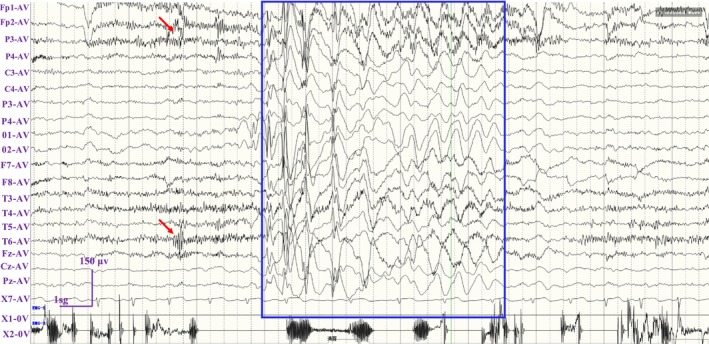

Results: A novel de novo intronic variant in SYNGAP1 (c.3582+2T>G) was indentified with clinical features suggestive of neurodevelopmental related disorders. Minigene splicing analysis demonstrated that this noncanonical splice site variant led to the activation of a cryptic acceptor splice site. Consequently, 101 base pairs of intron 16 were aberrantly retained in the mRNA, leading to a frameshift. This frameshift resulted in the introduction of a premature stop codon (TGA) in the coding sequence and the production of a truncated SYNGAP1 protein, potentially leding to loss of function and subsequent disruption of its biological roles.